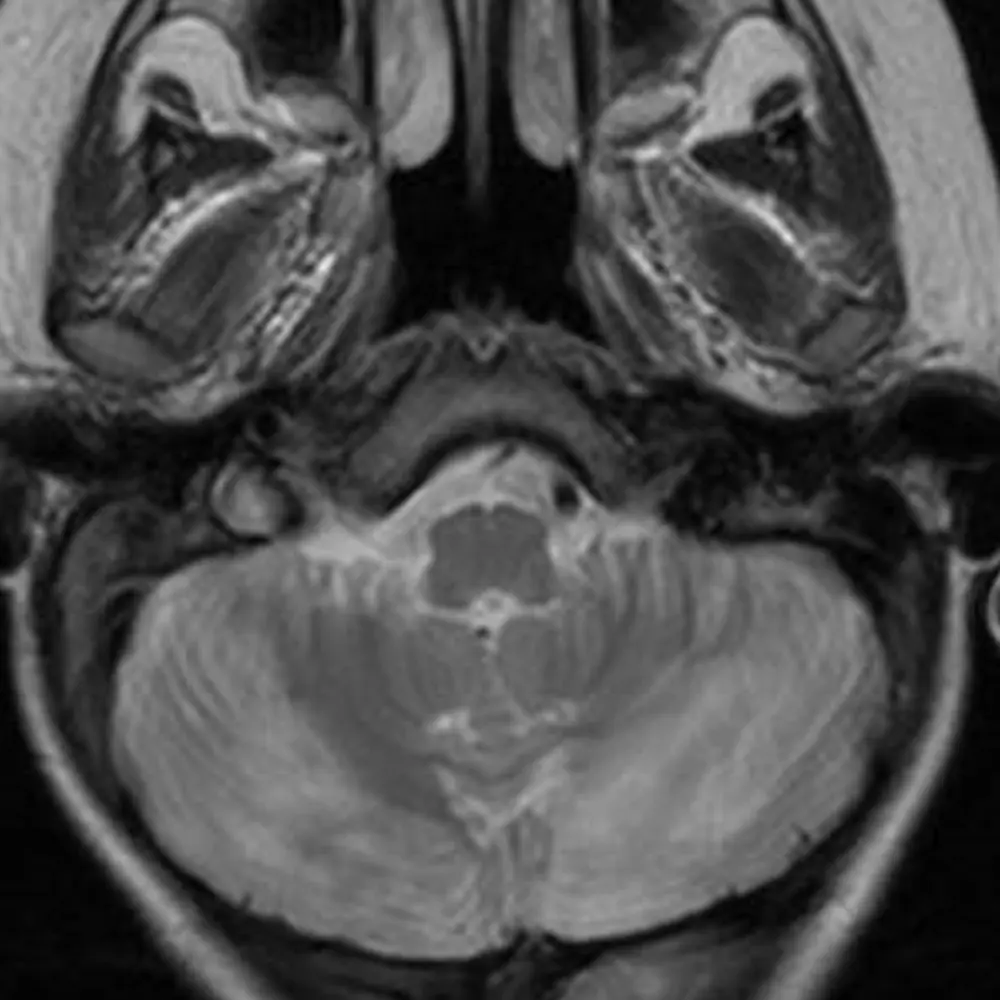

The cerebellum has two hemispheres and a central vermis (Figure 1). Each is divided into 3 lobes, and those lobes are divided into between 9 and 10 lobules.

The first step in understanding the cerebellum is to delineate the anterior, posterior, and flocculonodular lobes using the primary fissure and the posterolateral fissure (Figure 2B).